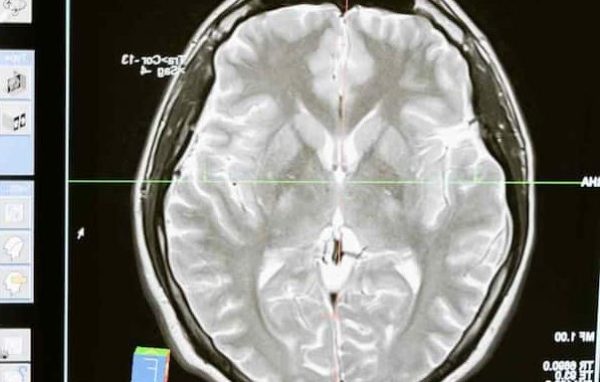

अभी तक हम यही मानते आए हैं कि याददाश्त यानी मेमोरी सिर्फ दिमाग का काम है. लेकिन अब एक नई रिसर्च ने इस सोच को पूरी तरह से बदल दिया है. न्यूयॉर्क यूनिवर्सिटी के वैज्ञानिक डॉ. निकोलाय कुकुश्किन की एक खास स्टडी में चौंकाने वाला दावा किया गया है कि हमारी याददाश्त सिर्फ दिमाग तक सीमित नहीं है, बल्कि किडनी, स्किन और अन्य अंगों की कोशिकाओं में भी मेमोरी जैसी प्रक्रिया होती है.

यह रिसर्च मशहूर साइंटिफिक जर्नल नेचर कम्युनिकेशन में प्रकाशित हुई है. इसमें बताया गया है कि हमारे शरीर की गैर-तंत्रिका कोशिकाएं यानी non-neural cells, जैसे कि किडनी की कोशिकाएं, भी कुछ जानकारी को याद रखने की क्षमता रखती हैं, जैसे न्यूरॉन करते हैं. तो चलिए जानते हैं कि रिसर्च में चौंकाने वाला दावा क्या है.